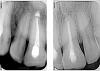

Desna911 Опубликовано 11 декабря, 2012 Поделиться Опубликовано 11 декабря, 2012 Вот снимки до и после: Ссылка на комментарий

pawa Опубликовано 11 декабря, 2012 Поделиться Опубликовано 11 декабря, 2012 если оценивать только картинку то стало лучше. лечили только один зуб? Ссылка на комментарий

Magdalena Опубликовано 11 декабря, 2012 Поделиться Опубликовано 11 декабря, 2012 (изменено) Перелечила бы зуб, который на снимке справа, верхушечная треть канала не плотно запломбирована. Изменено 11 декабря, 2012 пользователем Magdalena Ссылка на комментарий

Magdalena Опубликовано 11 декабря, 2012 Поделиться Опубликовано 11 декабря, 2012 (изменено) Гуттаперча сравнительно легко распломбировывается. Грозить может обострением в будущем, хотя на перелечивание итак гарантий не дают. По исходному снимку впечатление, что канал в верхушечной трети широкий + идет рассасывание верхушки корня + плюс не создали апикальный упор и гуттаперчивый штифт вышел за пределы корня. Возможно для пломбирования этой части канала нужно было выбрать другой способ, например Прорут, когда в этой части канала создается герметичная пробка из специального цемента. Изменено 11 декабря, 2012 пользователем Magdalena Ссылка на комментарий

Magdalena Опубликовано 12 декабря, 2012 Поделиться Опубликовано 12 декабря, 2012 Действительно, по этому снимку ситуация иная, корень не рассасывается и канал в верхушечной трети не широкий, поэтому можно и без Прорута. На коронки гарантии, как правило, дают, но в любом случае, за Вашу клинику отвечать не могу, спросите у врача. Ссылка на комментарий